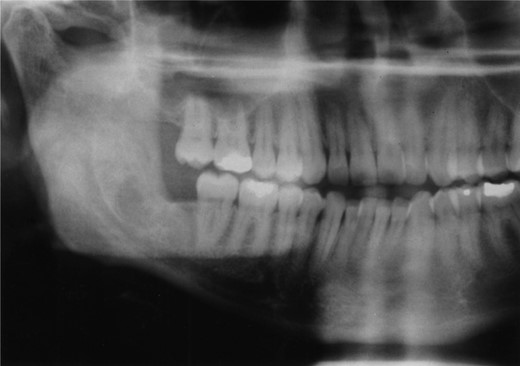

Radiographic examination over the following few months showed new bone formation and within 9 months of the initial biopsy the drain was expelled by formation of new bone (Fig. 3). One year after the commencement of treatment the patient was admitted for enucleation of the cystic remnant. At the time of this procedure a small cyst was removed from the right upper ramus and condylar neck, together, with a separate cyst associated with the lower right wisdom tooth. The patient made an uneventful post-operative recovery and histology revealed two KCOTs with a thick parakeratinized type of epithelium typical of radicular cysts.

Plain films along with CT scan, with 3 mm slices, were performed a further year later and showed good bone regeneration in the right ramus and condylar neck (Figs 4 and 5). No evidence of cystic recurrence was seen and no abnormalities within the adjacent soft tissues. High-resolution magnetic resonance imaging also confirmed the absence of cystic remnants. The patient has now been reviewed for 5 years and there is no evidence of recurrence.